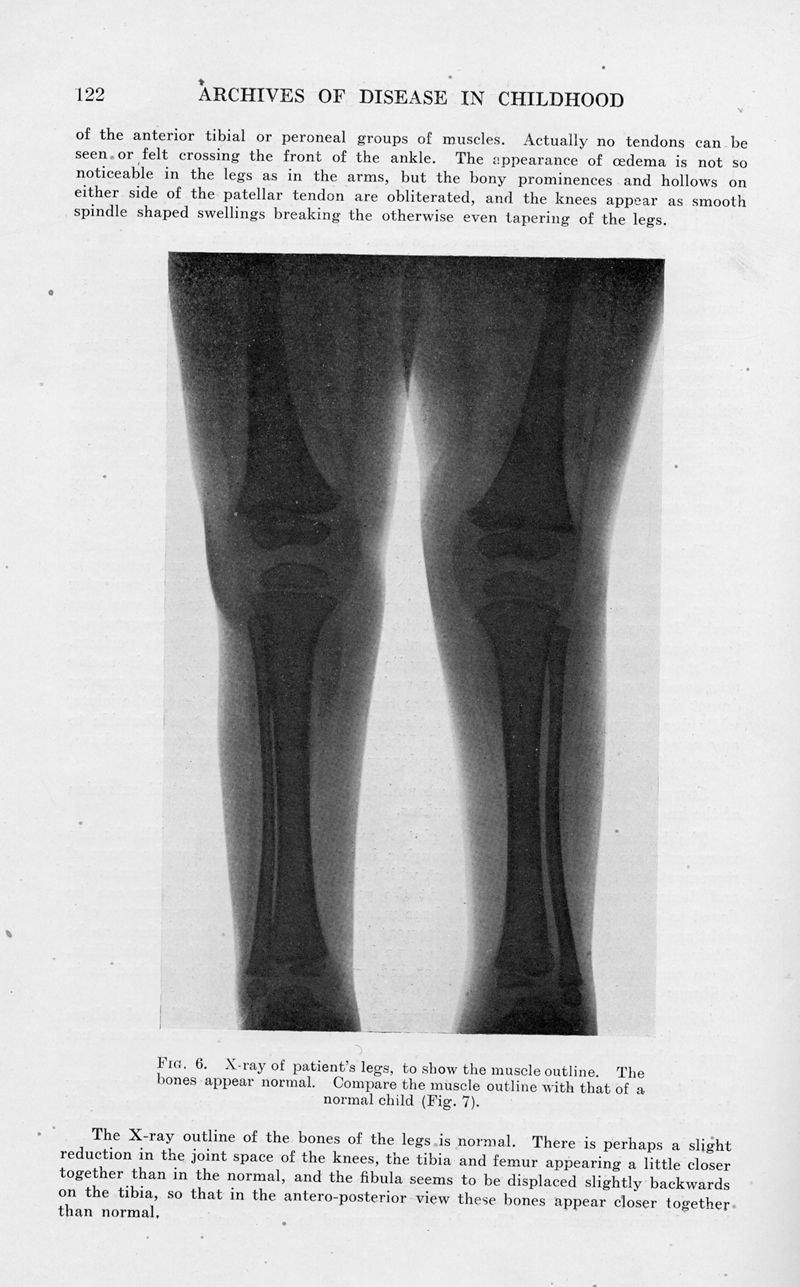

Amyoplasia congenita. (Multiple congenital articular rigidity : Arthrogryposis multiplex congenita)

In : Archives of Disease in Childhood, 1932, Vol. 7, pp. 117-36